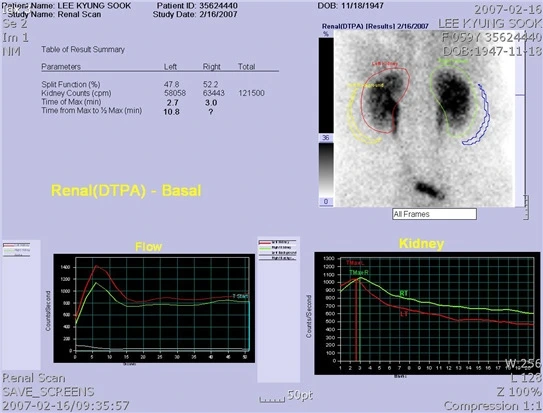

모니터를 보여주시며 오늘 한 검사는 양쪽 콩팥에 2200개의 방사성 동위원소를 넣고 절반으로 줄어드는 시간이 20분 이내인지 확인하는 검사였다고 하셨다. 아무래도 내가 이과 출신이라 그런지 의사 선생님이 결과 해석을 해주시기 전에도 한눈에 그래프가 뭘 의미하는 이해가 됐다. 두 개의 그래프 선이 일치하지 않으니 양 콩팥의 속도 차이는 있지만 9분, 15분 이내에 방사성 동위원소가 절반이 되었으니 둘 다 정상인 것으로 생각되었다. 그래도 선생님의 입으로 직접 듣고 확인받고 싶었다.

오른쪽 콩팥은 9분 만에 수치가 절반이 되었고 왼쪽은 15분 만에 절반이 됐어요. 속도 차이가 있지만 정상 범위입니다. 이제 제 얼굴 안 보셔도 됩니다.

참고로 방광요관재문합술을 받은 콩팥은 오른쪽이다. 수술받은 쪽이 기능이 더 좋다니! 실력이 좋으시군요, 선생님! ㅎ